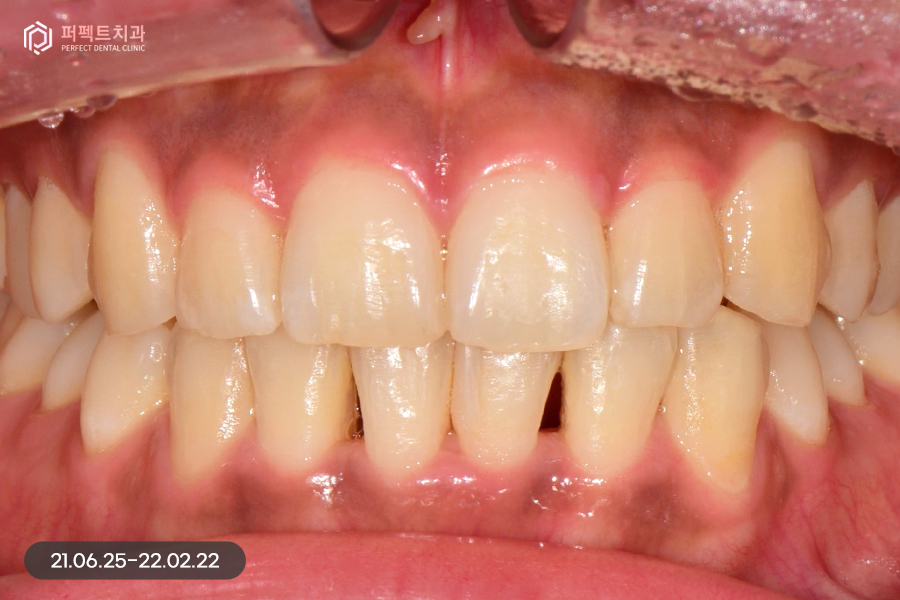

교정 후 치아가 가지런하게 펴졌는데, 교정을 하면 항상 생기는 문제점 중 하나가 바로 고르지 못한 치아들이 가지런하게 펴지면서 잇몸 사이 공간인 블랙트라이앵글입니다.

위 환자분도 마찬가지로 블랙트라이앵글이 발생했고, 이 공간을 해결함과 동시에 치아 색상도 하얗게 변화를 주길 원하셨습니다. 그렇기 때문에 위, 아래 6개 치아를 라미네이트 진행하였습니다.

삭제 후 사진을 보시면 경계 부분만 0.1~0.2mm 정도 다듬어서 최소삭제로 진행을 하였습니다. 마취 없이 시술을 하였고 다듬은 후 임시치아를 하지 않아도 일상생활에 심미적으로 큰 불편감이 없었습니다.

색상은 환자분께서 직접 고르신 색상이고, 사진으로 보았을 때에는 많이 밝은 것처럼 보이지만 뒷 치아와 크게 어색하지 않으면서 환자분과 잘 어울리는 치아색상이었습니다.

치아를 0.10.2mm 정도 다듬은 후 0.20.3mm의 라미네이트를 부착하게 된다면 0.1~0.2mm 정도의 볼륨감이 생길 수 있는데 치아가 가지런한 상태에서 이 정도의 느낌 차이는 괜찮다고 볼 수 있습니다.